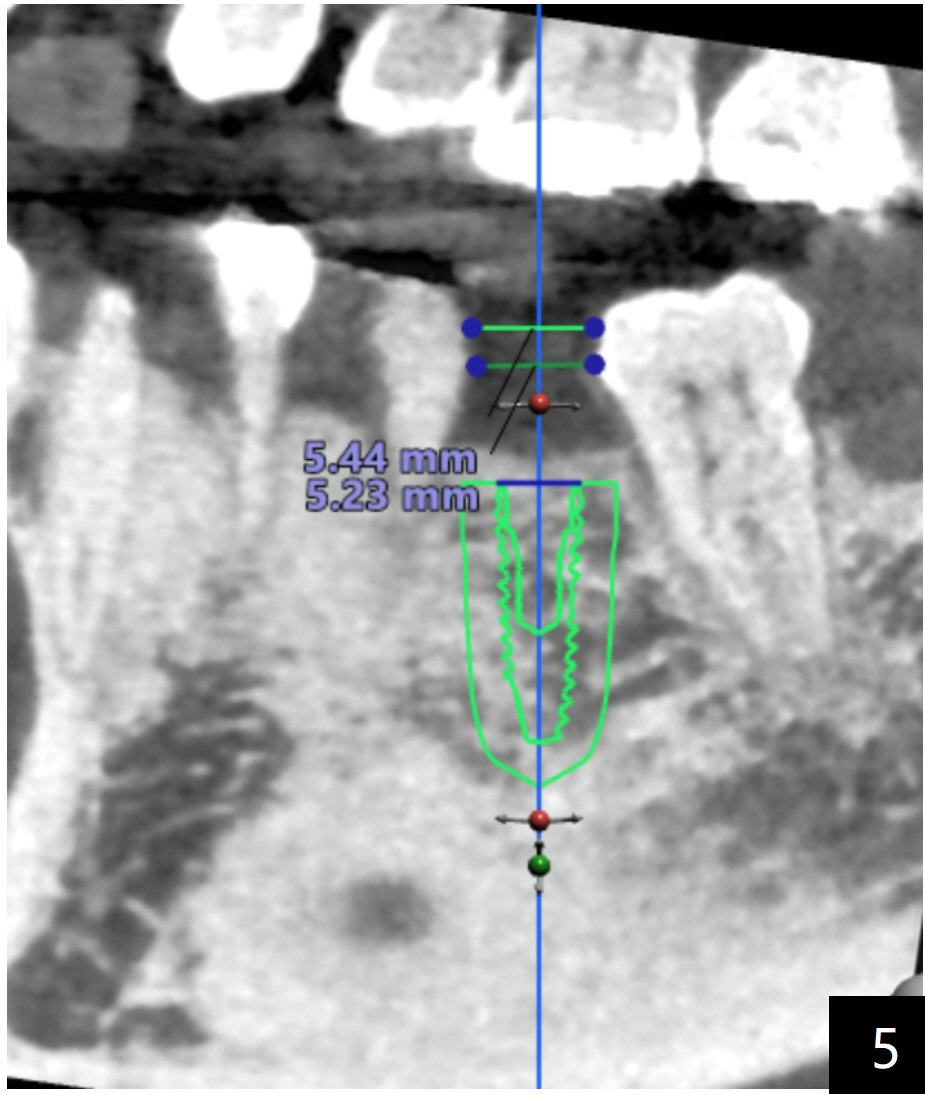

The space would be enough if we use narrow guide kit (Fig.5).  However as the bone width is narrow you may have to consider ridge split (Fig.6).